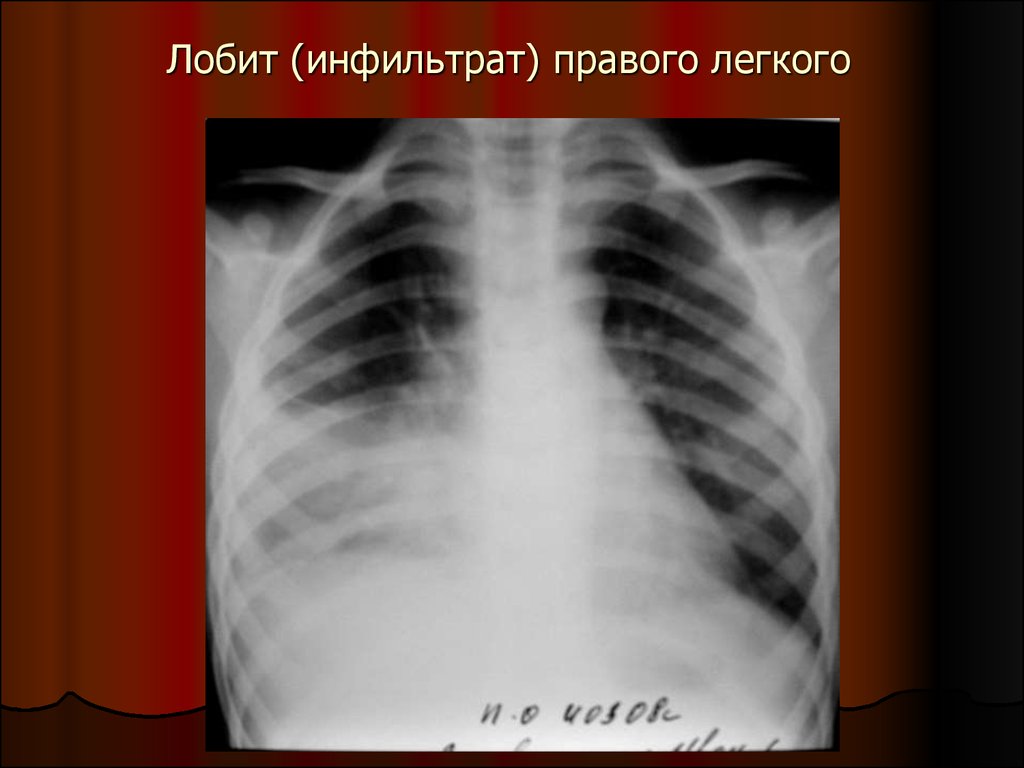

Симптомы и лечение инфильтративного туберкулеза легких

Раздел: Снимки-откровения